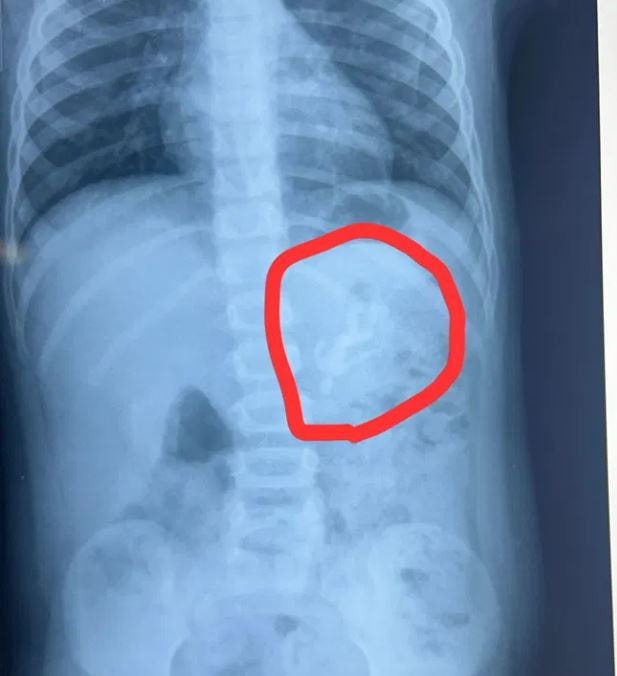

Các bác sĩ đã tiến hành chụp X-quang và phát hiện một điều đáng ngạc nhiên và đáng báo động - toàn bộ món đồ chơi bằng nhựa đã mắc kẹt bên trong dạ dày của đứa trẻ. Đó không phải là một mảnh vỡ mà là một hình đồ chơi hoàn chỉnh giống nhân vật Hulk trong phim Avengers, với đầu, tay và chân còn nguyên vẹn.